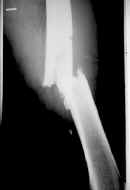

Caso clínico No 2. Paciente de 60 años con fractura del tercio medio y distal del fémur; consolidación posquirúrgica a las 30 semanas.